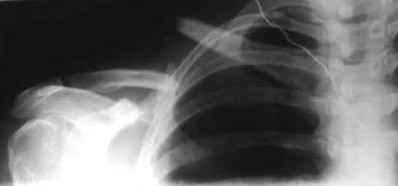

A 70-year-old woman falls down a flight of stairs and sustains the injury shown in Figures A and B to her dominant upper extremity. She lives alone and has no other medical history. Which of the following surgical options is best to minimize complications for this fracture pattern?

This patient has a complex proximal humerus fracture with metaphyseal comminution and poor bone stock. Cemented reverse total shoulder arthroplasty (rTSA) using a long stem prosthesis and tuberosity repair is indicated.

Proximal humerus fragility fractures are hard to treat because of comminution and poor bone stock. AVN is common with glenohumeral fracture-dislocation. Hemiarthroplasty (and standard total shoulder arthroplasty, TSA) is unreliable because of dependence on tuberosity healing. rTSA is recommended for fractures in patients >70 years with severely comminuted fractures, high likelihood of head AVN, and poor tuberosity bone quality (osteoporosis or comminution).

Figures A and B are AP radiograph and 3D reformatted CT scan showing comminuted proximal humerus fracture dislocation. Illustration A shows rTSA performed with distal cementation of a long stem prosthesis and cerclage fixation of the proximal shaft and the tuberosity fragments.